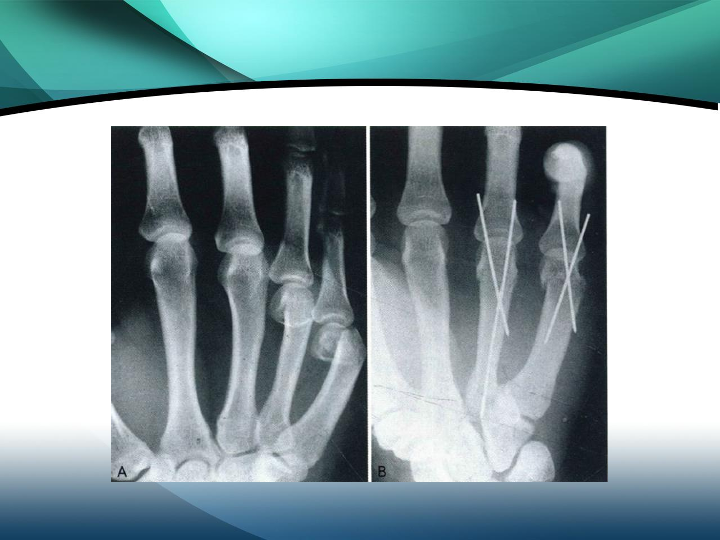

掌骨骨折